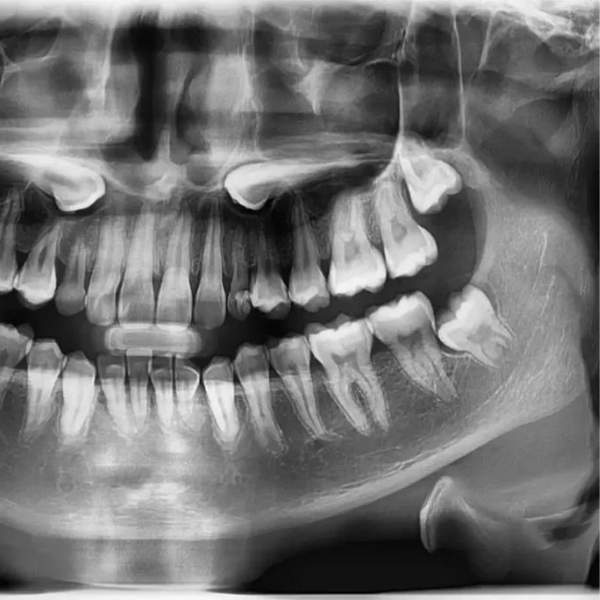

1. Initial Consultation: Schedule an appointment with one of our dentists to evaluate your wisdom teeth. During this visit, we will conduct a thorough examination, including X-rays, to assess the position and condition of your wisdom teeth.